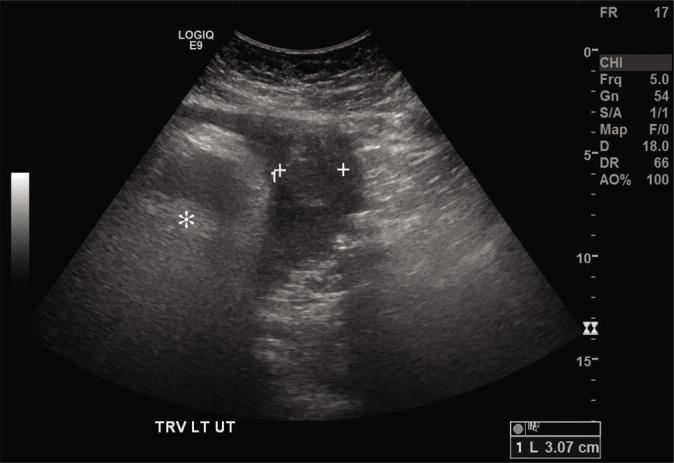

We describe a case of a 63-year-old woman referred to an oncologist for treatment of endometrial adenocarcinoma. A computed tomography scan revealed the incidental finding of a 11.5 × 10.5 × 9.0 cm myomatous mass in the uterine corpus adjacent to, yet uninvolved with, the adenocarcinoma. Histopathological analysis confirmed the mass to be a lipoleiomyoma, a rare single variant of lipoma. These fatty tumors present similar to leiomyomas and as such are generally not harmful; however, the potential exists for diagnostic confusion with other uterine tumors. This case serves to further illuminate the findings associated with these rare tumors.

我们描述了一例63岁女性因子宫内膜腺癌转诊至肿瘤学家处接受治疗的病例。计算机断层扫描偶然发现子宫体有一个11.5×10.5×9.0厘米的肌瘤样肿块,与腺癌相邻但未受其影响。组织病理学分析证实该肿块为脂肪平滑肌瘤,这是一种罕见的脂肪瘤单一变体。这些脂肪性肿瘤的表现与平滑肌瘤相似,因此通常无害;然而,与其他子宫肿瘤存在诊断混淆的可能性。本病例有助于进一步阐明与这些罕见肿瘤相关的发现。